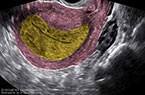

Grossesse môlaire volumineuse de 739 ml de volume Grossesse môlaire volumineuse de 739 ml de volume Grossesse môlaire volumineuse de 739 ml de volume